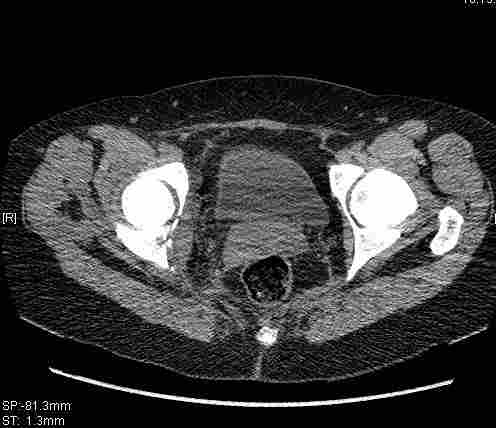

[Ortho] [1/2] Re: Т-образный перелом вертлужной впадины

Удалось сегодня вывести пациентку в соседнюю больницу, где есть кт.

Срезы сделаны  только горизонтальные.